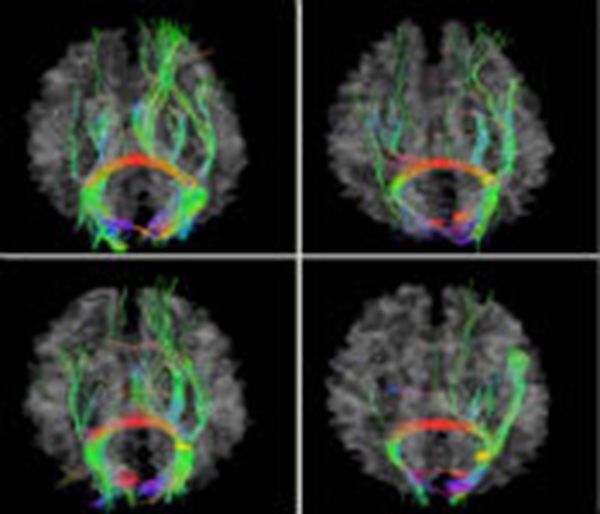

People who are out of shape in midlife may end up with smaller brain volume as they age compared to peers who exercise regularly, a according to a U.S. study.

Almost two decades later, researchers put them back on the treadmill, and also did magnetic resonance imaging (MRI) scans of their brains. At this point, they were around 58 years old.